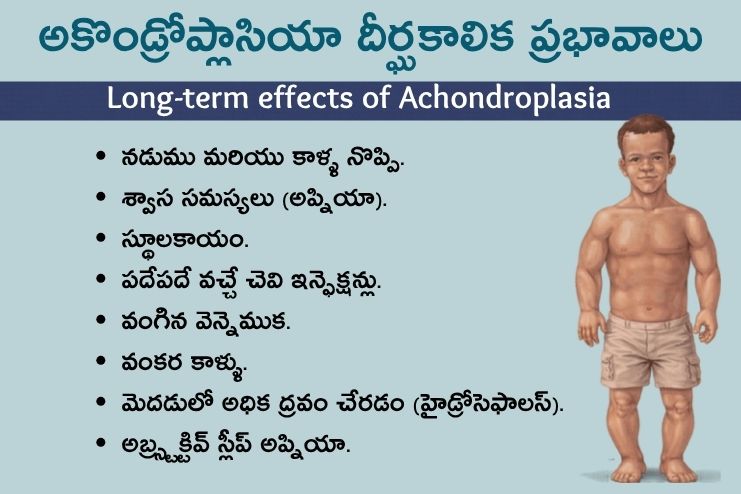

శరీరంపై అకొండ్రోప్లాసియా దీర్ఘకాలిక ప్రభావాలు? Long-term effects of achondroplasia?

- నడుము మరియు కాళ్ళ నొప్పి.

- శ్వాస సమస్యలు (అప్నియా).

- స్థూలకాయం.

- పదేపదే వచ్చే చెవి ఇన్ఫెక్షన్లు.

- వంగిన వెన్నెముక.

- వంకర కాళ్ళు.

- మీ మెదడులో అధిక ద్రవం చేరడం (హైడ్రోసెఫాలస్).

- అబ్స్ట్రక్టివ్ స్లీప్ అప్నియా.